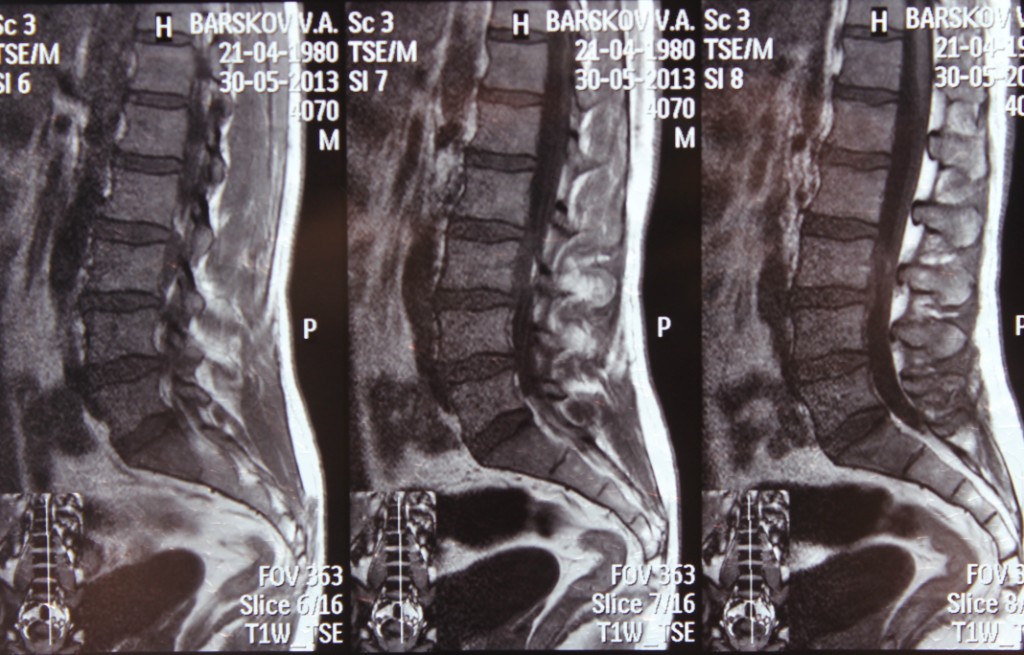

Рентгеновские снимки крестцово-копчикового отдела позвоночника